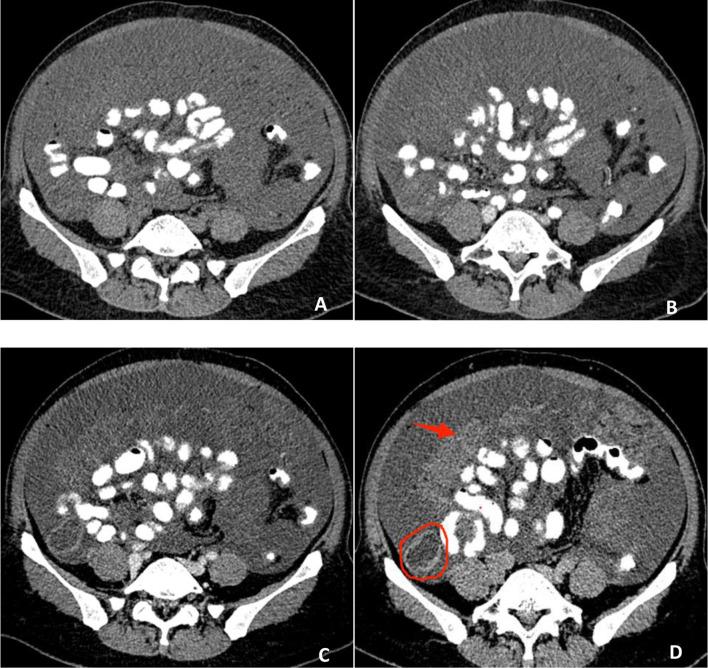

A radiomics-based interpretable model integrating delayed-phase CT and clinical features for predicting the pathological grade of appendiceal pseudomyxoma peritonei.

This study aimed to develop an interpretable machine learning model integrating delayed-phase contrast-enhanced CT radiomics with clinical features for noninvasive prediction of pathological grading in appendiceal pseudomyxoma peritonei (PMP), using Shapley Additive Explanations (SHAP) for model interpretation.

This retrospective study analyzed 158 pathologically confirmed PMP cases (85 low-grade, 73 high-grade) from January 4, 2015 to April 30, 2024. Comprehensive clinical data including demographic characteristics, serum tumor markers (CEA, CA19-9, CA125, D-dimer, CA-724, CA-242), and CT-peritoneal cancer index (CT-PCI) were collected. Radiomics features were extracted from preoperative contrast-enhanced CT scans using standardized protocols. After rigorous feature selection and five-fold cross-validation, we developed three predictive models: clinical-only, radiomics-only, and a combined clinical-radiomics model using logistic regression. Model performance was evaluated through ROC analysis (AUC), Delong test, decision curve analysis (DCA), and Brier score, with SHAP values providing interpretability.

The combined model demonstrated superior performance, achieving AUCs of 0.91 (95%CI:0.86-0.95) and 0.88 (95%CI:0.82-0.93) in training and testing sets respectively, significantly outperforming standalone models (P < 0.05). DCA confirmed greater clinical utility across most threshold probabilities, with favorable Brier scores (training:0.124; testing:0.142) indicating excellent calibration. SHAP analysis identified the top predictive features: wavelet-LHH_glcm_InverseVariance (radiomics), original_shape_Elongation (radiomics), and CA-199 (clinical).